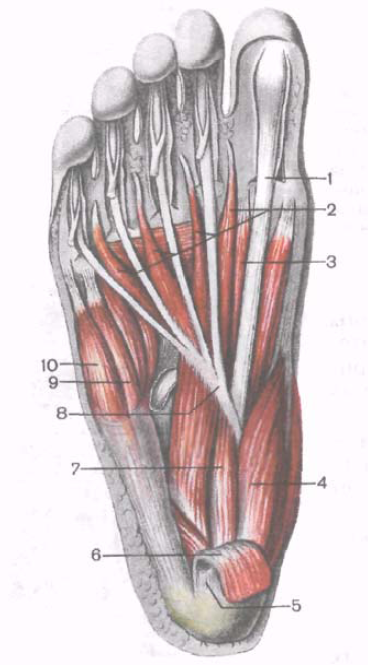

Анатомия подошвенной мышцы голени: подробное рассмотрение